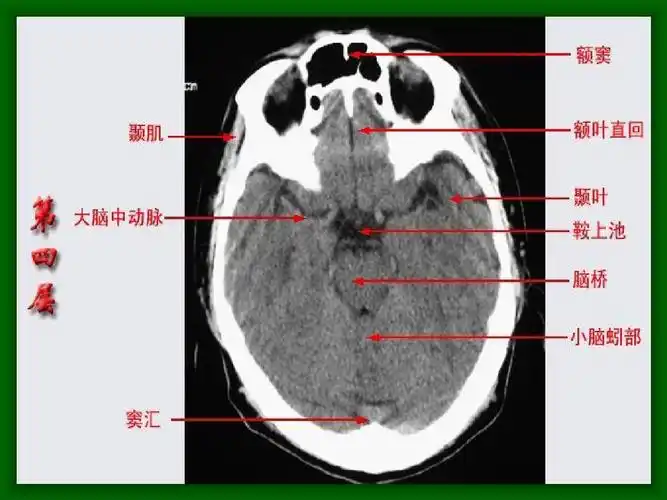

医学急救头颅ct解剖图片

10张图搞定正常头颅ct断层解剖